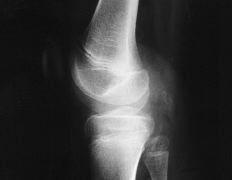

En todos los casos la exploración física mostró un derrame articular con hipertrofia sinovial. Existía una actitud en flexo en todos los casos (Fig. 1) y limitación de la flexión en todos ellos (Tabla 1). Sólo en tres casos la articulación era evidentemente dolorosa a la palpación, presentando aspecto flogótico. En el estudio radiológico se apreciaba osteoporosis yuxtaarticular de distinta intensidad, con edema de partes blandas, conservación de la interlínea articular en cuatro casos y erosiones en platillos tibiales y cóndilos en tres de los casos. En una paciente diagnosticada previamente de artritis reumatoide la relativamente buena preservación de la interlínea articular llevó a realizar una biopsia sinovial.

ABFigura 1. A: Aspecto clínico de la rodilla de una niña de 9 años con tuberculosis articular. Se aprecia el discreto flexo con derrame, pero sin signos flogósicos evidentes. B: Radiografía lateral de la rodilla de la misma paciente. Se puede apreciar la tumefacción sinovial en la región poplítea, aunque no existe una osteoporosis marcada.